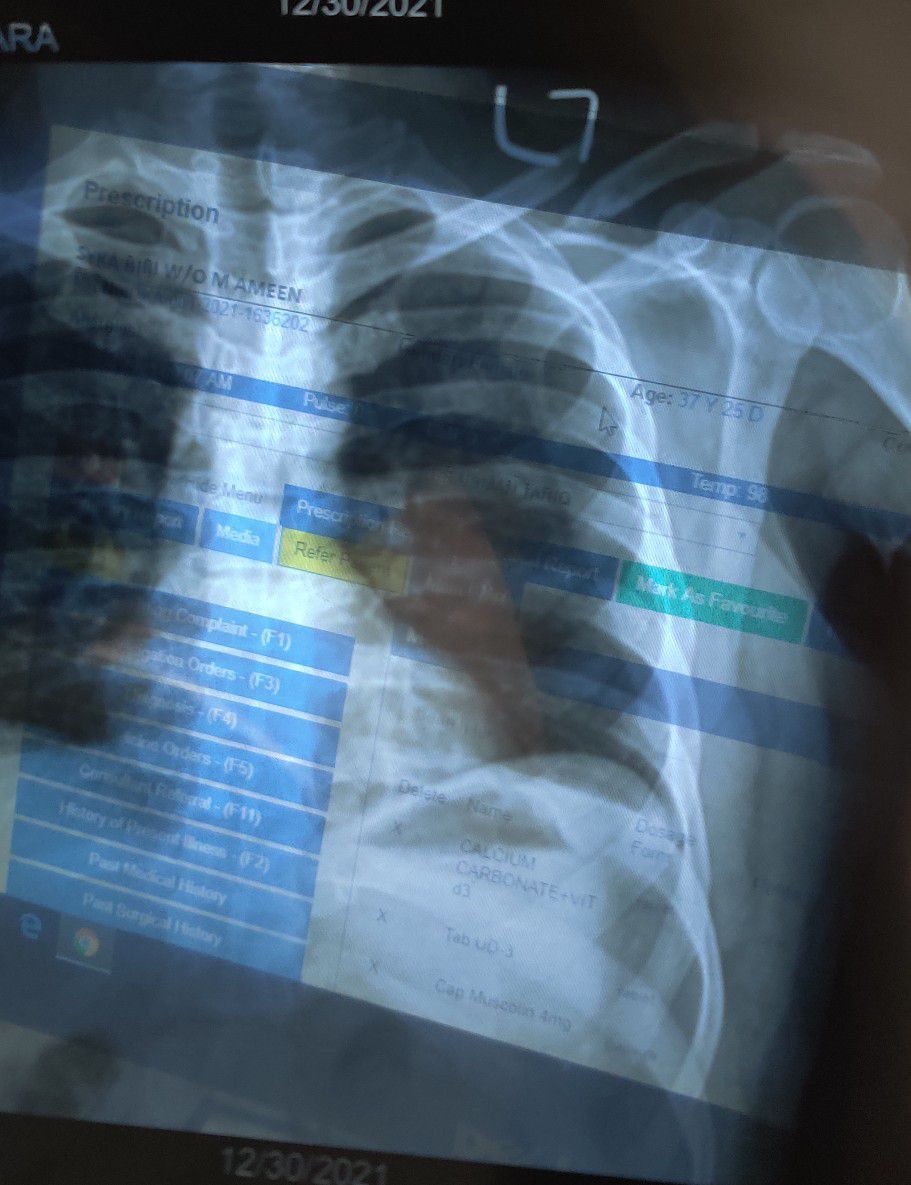

L clavicle Fracture

Xray

Ortho

Clavicle